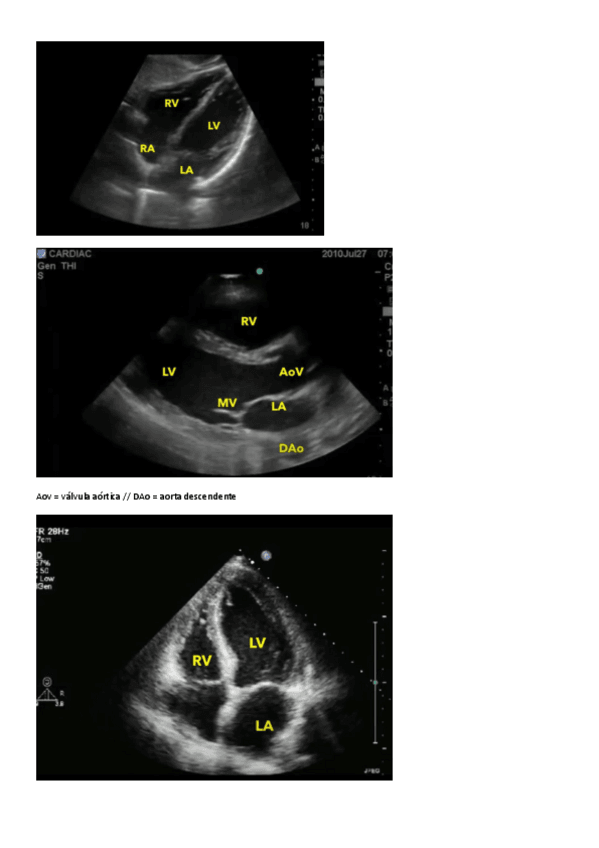

He publicado nuevos apuntes de 2º Anatomía II: ECOGRAFIA-EN-ANATOMIA.pdf

2 páginas